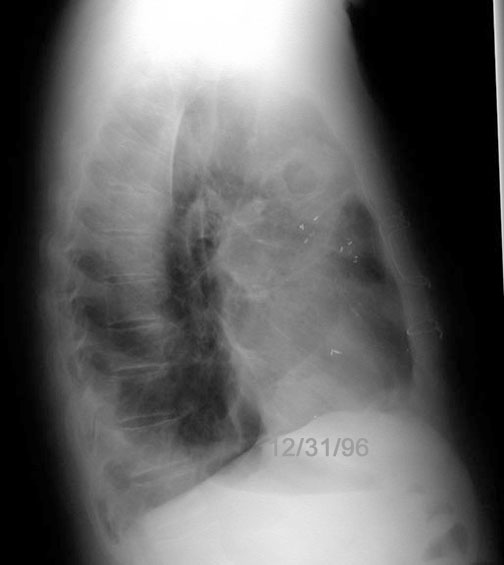

Case 30

Lateral

Initial PA

Initial lateral

Labeled Image What are the common segments for aspiration lung abscess?

What are the types of aspiration?